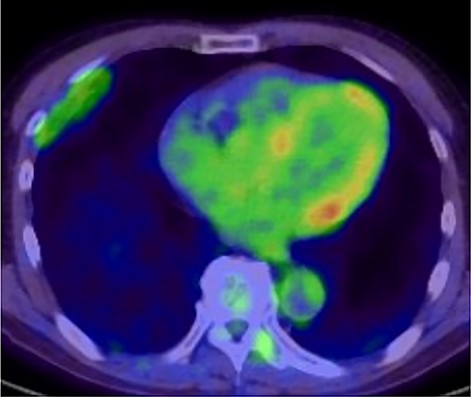

A 72-year-old man with a history of hypertension and left renal cancer (Stage I) was referred to us with a mass in the right chest wall on post-operative follow-up chest computed tomography (CT) for renal cancer. He had a smoking history of 20 pack-years and had no exposure to environmental fumes or dust. Physical examination results were unremarkable. The laboratory findings were within normal limits. Pulmonary function tests and cardiovascular examinations revealed normal results. Chest CT revealed mixed density mass (8.0 × 5.0 × 3.0 cm) located in front of thoracic wall in the third to sixth right intercostal space. The tumor can be revealed as thoracic wall fat (7.8 × 4.8 × 1.2 cm) on CT 1 year before (not considered as abnormal), and it was progressively increased in size and the density changed (Fig. 1A and B). Magnetic resonance imaging (MRI) showed a fatty mass of heterogenic density. T2 high foci (Fig. 2A) and irregular marginal enhancement of the tumor were observed (Fig. 2B). Maximal standard uptake value (SUVmax) of 18F-fluorodeoxyglucose positron emission tomography (FDG-PET) was 3.78 (Fig. 3). Based on these radiological image findings, we scheduled surgery with suspicion of liposarcoma. During the surgery, the patient was placed in the lateral decubitus position. We made 1.5-cm incision in the sixth intercostal space along the posterior axial line for thoracoscopy. We found dense adhesions between the chest wall tumor, lung (front part of all three lobes of the right lung) and diaphragm. We made a 30-cm incision in the fourth intercostal space and resected the tumor along with lung (wedge resection of the front part of all three lobes of the right lung), diaphragm and third to sixth ribs and intercostal muscle. The chest wall defect was 25 × 15 cm and the diaphragm defect was 8 × 5 cm. For reconstruction, the mesh was placed and sutured to the diaphragm and the chest wall. Pathological examination revealed the well-circumscribed tumor with fibrous adhesion between the ribs, lung and diaphragm (Fig. 4A). Microscopically, the tumor consisted of mature fat tissue. There were fat necrosis inflammatory changes in the marginal area of the tumor with foamy macrophages and multinucleated giant cells (Fig. 4B and C). Fluorescence in situ hybridization examination for murine double-minute 2 was negative. Based on these findings, a chest wall lipoma was diagnosed. The post-operative course was uneventful. The patient was followed up for 24 months without evidence of recurrence.

18F-FDG-PET uptake by the tumor; maximum standard uptake value was 3.78.

In the present case, tumor enlargement with heterogenic change of the density, thickened septa >2 mm, prominent foci of high T2 signal and prominent areas of enhancement on MRI were seen on preoperative CT and MRI. In addition, the SUVmax of FDG-PET was higher than that of simple lipoma (SUVmax = 3.78). These findings led to a misdiagnosis for liposarcoma. Furthermore, intraoperative findings of dense adhesion between the tumor and surrounding structures strengthen our suspicion of liposarcoma. We could not find another case of intrathoracic lipoma of the chest wall with density change on radiological image and dense adhesion between the surrounding structures.